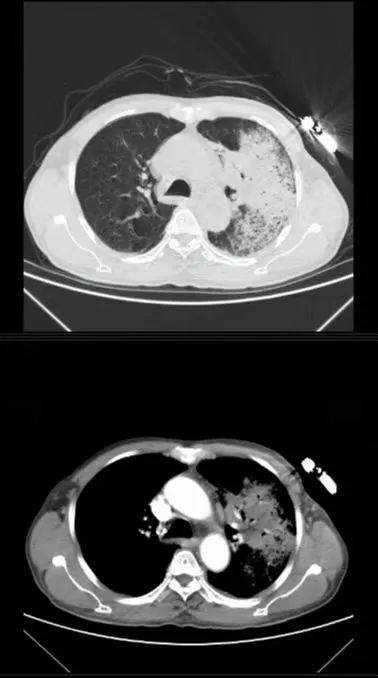

入院时,患者乏力、发热,胸闷、咯血,为了尽快找到病因,呼吸感染学组专家立即为患者完善相关实验室检查和影像学检查,并召开专题研究会,对黎先生的病情进行细致的研究和讨论。根据患者病史、症状和体征,初步判断其是因某种特殊致病菌感染导致肺部炎症,极有可能是饲养家禽引起的感染。

考虑到传统的检测方法阳性率低,周期长,呼吸感染学组专家决定选取气管镜肺泡灌洗液进行高通量测序mNGS检测,以便快速精准锁定病原。最终,检查结果验证了专家们的判断,黎先生感染了鹦鹉热衣原体!明确了病因,专家们立即对黎先生进行对症治疗,经过精准治疗,患者很快恢复出院。

气管镜图:左肺上叶

气管镜图:气管隆突